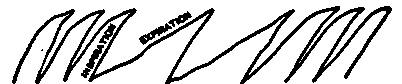

| 23. | Normal diaphragm curve in normal breathing | 577 |

| 24. | Curve in diaphragm before and during talking by a stutterer | 577 |